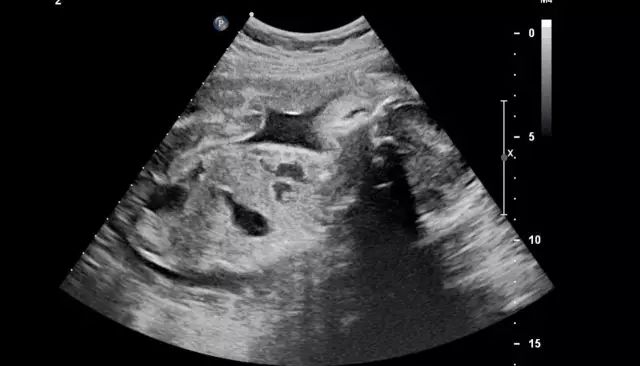

终于轮到我了。我绷紧神经,先到床头拿了一张纸放在床中央,坐上去准备脱右腿裤子时,突然发现自己穿了靴子,两只都脱,会耗时过长,大脑飞速转过医生等得不耐烦的样子,顿时慌乱了。“两只鞋子都要脱吗?”我问医生,问完我就后悔了。等待她的回答很漫长,长到我有足够时间把它们都脱下来。医生最终也没理我,撕开一个好像安全套似的袋子,取出套子,套在一根长长的检查器上,然后板着脸把它插进阴部。

我的心情非常复杂,不敢喊疼又有些恐惧。“多大了?”医生面无表情问我。“我吗?”我不清楚她问的是我,还是腹中的胎儿。

“几个月了?”她补充了一句。

“我不知道,医生没说,我自己查是5周。”

“还看不到。”她拔出检查器,打出检查单,“下一个。”